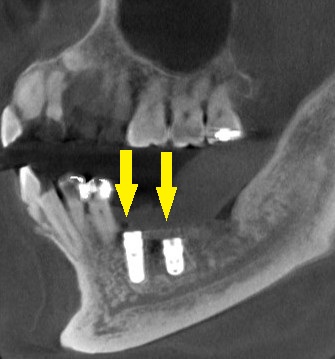

本日、2本のインプラント埋入と、骨造成術を行いました。

下の写真3段目が手術後のCTです。

インプラントと神経までの距離は確保され、インプラント上方は人工骨で覆われています。